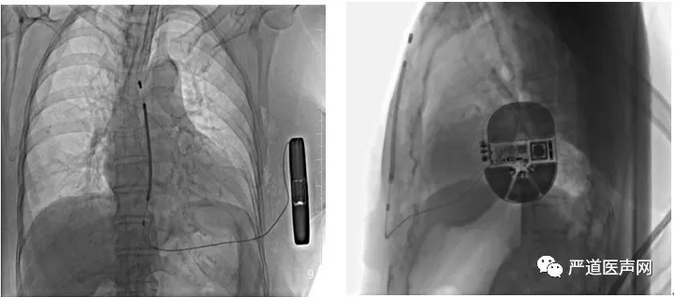

术后影像

手术在全身麻醉下进行,于左侧第5肋间沿腋中线走形切开皮肤7厘米,逐层分离皮下组织至筋膜层,作囊袋确保足够深度来容纳装置。于剑突下切开皮肤2厘米,逐层分离皮下组织至筋膜层,通过隧道穿引针连接囊袋,再沿胸骨向上约14厘米处切开皮肤1厘米,逐层分离皮下组织至筋膜层,通过隧道穿引针连接剑突下切口,使用隧道穿引针将45厘米长的3401除颤电极从囊袋经隧道送至剑突下切口,固定电极中段,再使用隧道穿引针将电极经隧道送至胸骨上方切口,固定头端。连接脉冲发生器,置入囊袋内,逐层缝合皮下组织及皮肤,术区纱布覆盖,包扎,弹力绷带加压包扎止血。 术后测试,除颤阻抗64欧姆。手术圆满成功,耗时1小时。